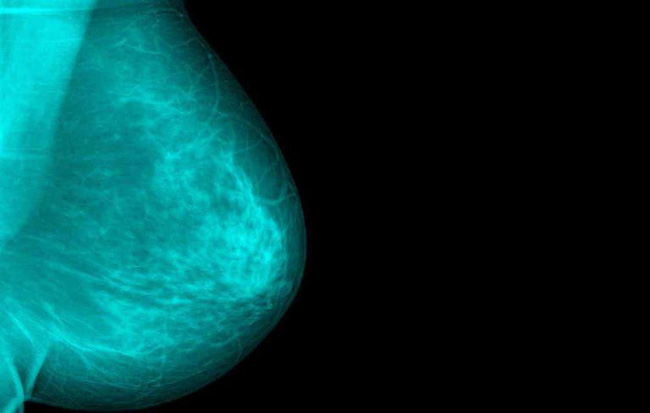

29/08/2018 15:57Chủ quan khi thấy vết ố màu xanh lá dính ở mặt trước của áo sơ mi, người phụ nữ giật mình khi biết đã bị bệnh nặng

Có thể nhiều người sẽ lấy làm lạ khi nghe nói tới triệu chứng này nhưng quả thực nó không phải là hiếm gặp. Theo nghiên cứu sơ bộ được trình bày tại (NCRI) 2016 - Hội nghị Viện Nghiên cứu Ung thư quốc gia của Vương quốc Anh, trường hợp như Megan không phải là duy nhất. Theo thống kê, cứ 6 phụ nữ phát hiện ra bệnh ung thư vú thì có 1 người có những triệu chứng không phổ biến và khó nhận ra. Những triệu chứng như: Núm vú bất thường, giảm cân đột ngột, có khối u ở ngực... được coi là triệu chứng rõ ràng, dễ nhận biết.

Bác sĩ Neelima Denduluri, chủ tịch của Ủy ban Ung thư Mạng lưới Ung thư Hoa Kỳ, nói rằng: Ngoài việc chụp quang tuyến vú và kiểm tra sức khỏe hàng năm, chị em cần tự kiểm tra bằng cách theo dõi xem có những triệu chứng lạ hay biểu hiện bất thường nào đó ở ngực hay không, kể cả những người không có cục u nào ở ngực.